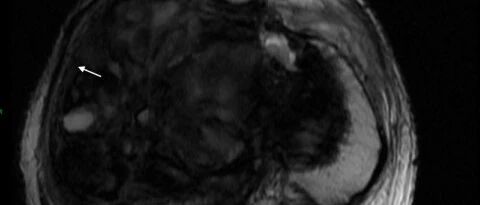

颅内多发动脉瘤长期随访一例

病例

2025-10-02